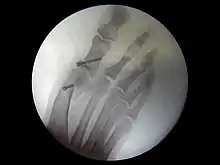

Bilan radiographique

Le diagnostic est avant tout clinique, mais des radiographies sont indispensables pour mesurer la déformation et adapter la technique chirurgicale aux spécificités du patient. Les radiographies doivent être effectuées de façon rigoureuse : clichés d'avant-pied de face, profil, et 3/4, patient debout en charge. Ce dernier critère est indispensable car le squelette du pied adopte des positions dans l'espace qui diffèrent selon que le poids du corps repose ou non sur lui. C'est l'état du squelette debout en charge qui doit guider le geste chirurgical.

Techniques opératoires

Au cours d'une intervention chirurgicale, plusieurs types de corrections peuvent être apportées, isolément ou de manière combinée :

Du point de vue de la technique pure, l'opération peut être menée selon plusieurs modalités :

- chirurgie classique : le chirurgien incise la peau en regard des zones à traiter ;

- chirurgie mini-invasive[7] : les techniques sont adaptés pour permettre d'effectuer les mêmes gestes, mais par des incisions (et donc des cicatrices) plus petites et en préservant mieux les tissus sous-cutanés ;

- chirurgie percutanée[8] : les avancées techniques les plus récentes permettent de pratiquer les gestes chirurgicaux à travers la peau. La taille des incisions ne dépasse alors pas quelques millimètres.